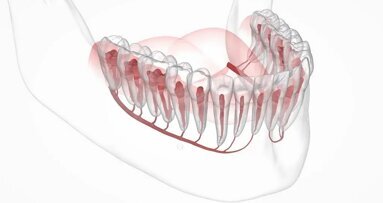

Houston, USA: Pacienti, kteří trpí ztrátou kosti dolní čelisti zapříčiněnou rakovinou, infekcí, úrazem nebo vrozeným onemocněním, žijí s kostními defekty, jež jsou esteticky a funkčně problematické. Vědci z univerzity v Rice vyvinuli techniku vytváření tkáně přizpůsobené konkrétnímu defektu: spočívá v implantování 3D tištěného bioreaktoru do žebra. Kmenové buňky a krevní cévy z žebra vrostou do přirozeného kostního materiálu, který je přizpůsoben pacientovi a může být transplantován do dolní čelisti.

Cílem výzkumu bylo zdokonalit kraniofaciální rekonstrukci využitím přirozených hojivých schopností těla. Tato technika byla vyvinuta proto, aby nahradila současné techniky rekonstrukce, které využívají autogenních kostních štěpů odebraných z různých oblastí, jako je dolní končetina, kyčle a rameno.

Vědci vytvořili obdélníkový defekt v dolních čelistech ovcí. Vyrobili šablonu pro 3D tisk a vytiskli implantovatelnou formu a distanční vložku, obojí z PMMA, známého také jako kostní cement. Úkolem distanční vložky bylo podporovat hojení a zabránit zjizvené tkáni, aby zaplnila oblast defektu.

Ze zvířecího modelu žebra odstranili dostatek kosti, aby odkryli periost, který sloužil jako zdroj kmenových buněk a cév pro implantaci štěpového materiálu do formy. Testované skupiny dostaly rozdrcenou kost žebra a syntetické materiály na bázi fosforečnanu vápenatého tvořící biologicky kompatibilní základ štěpu.

Forma s otevřenou částí žebra pro vytvoření těsného rozhraní zůstala na místě po dobu devíti týdnů, pak byla odebrána a přenesena do místa defektu, kde nahradila distanční vložku. Na zvířecích modelech se nová kost propojila se starou a kolem narostly měkké tkáně a oblast pokryly.